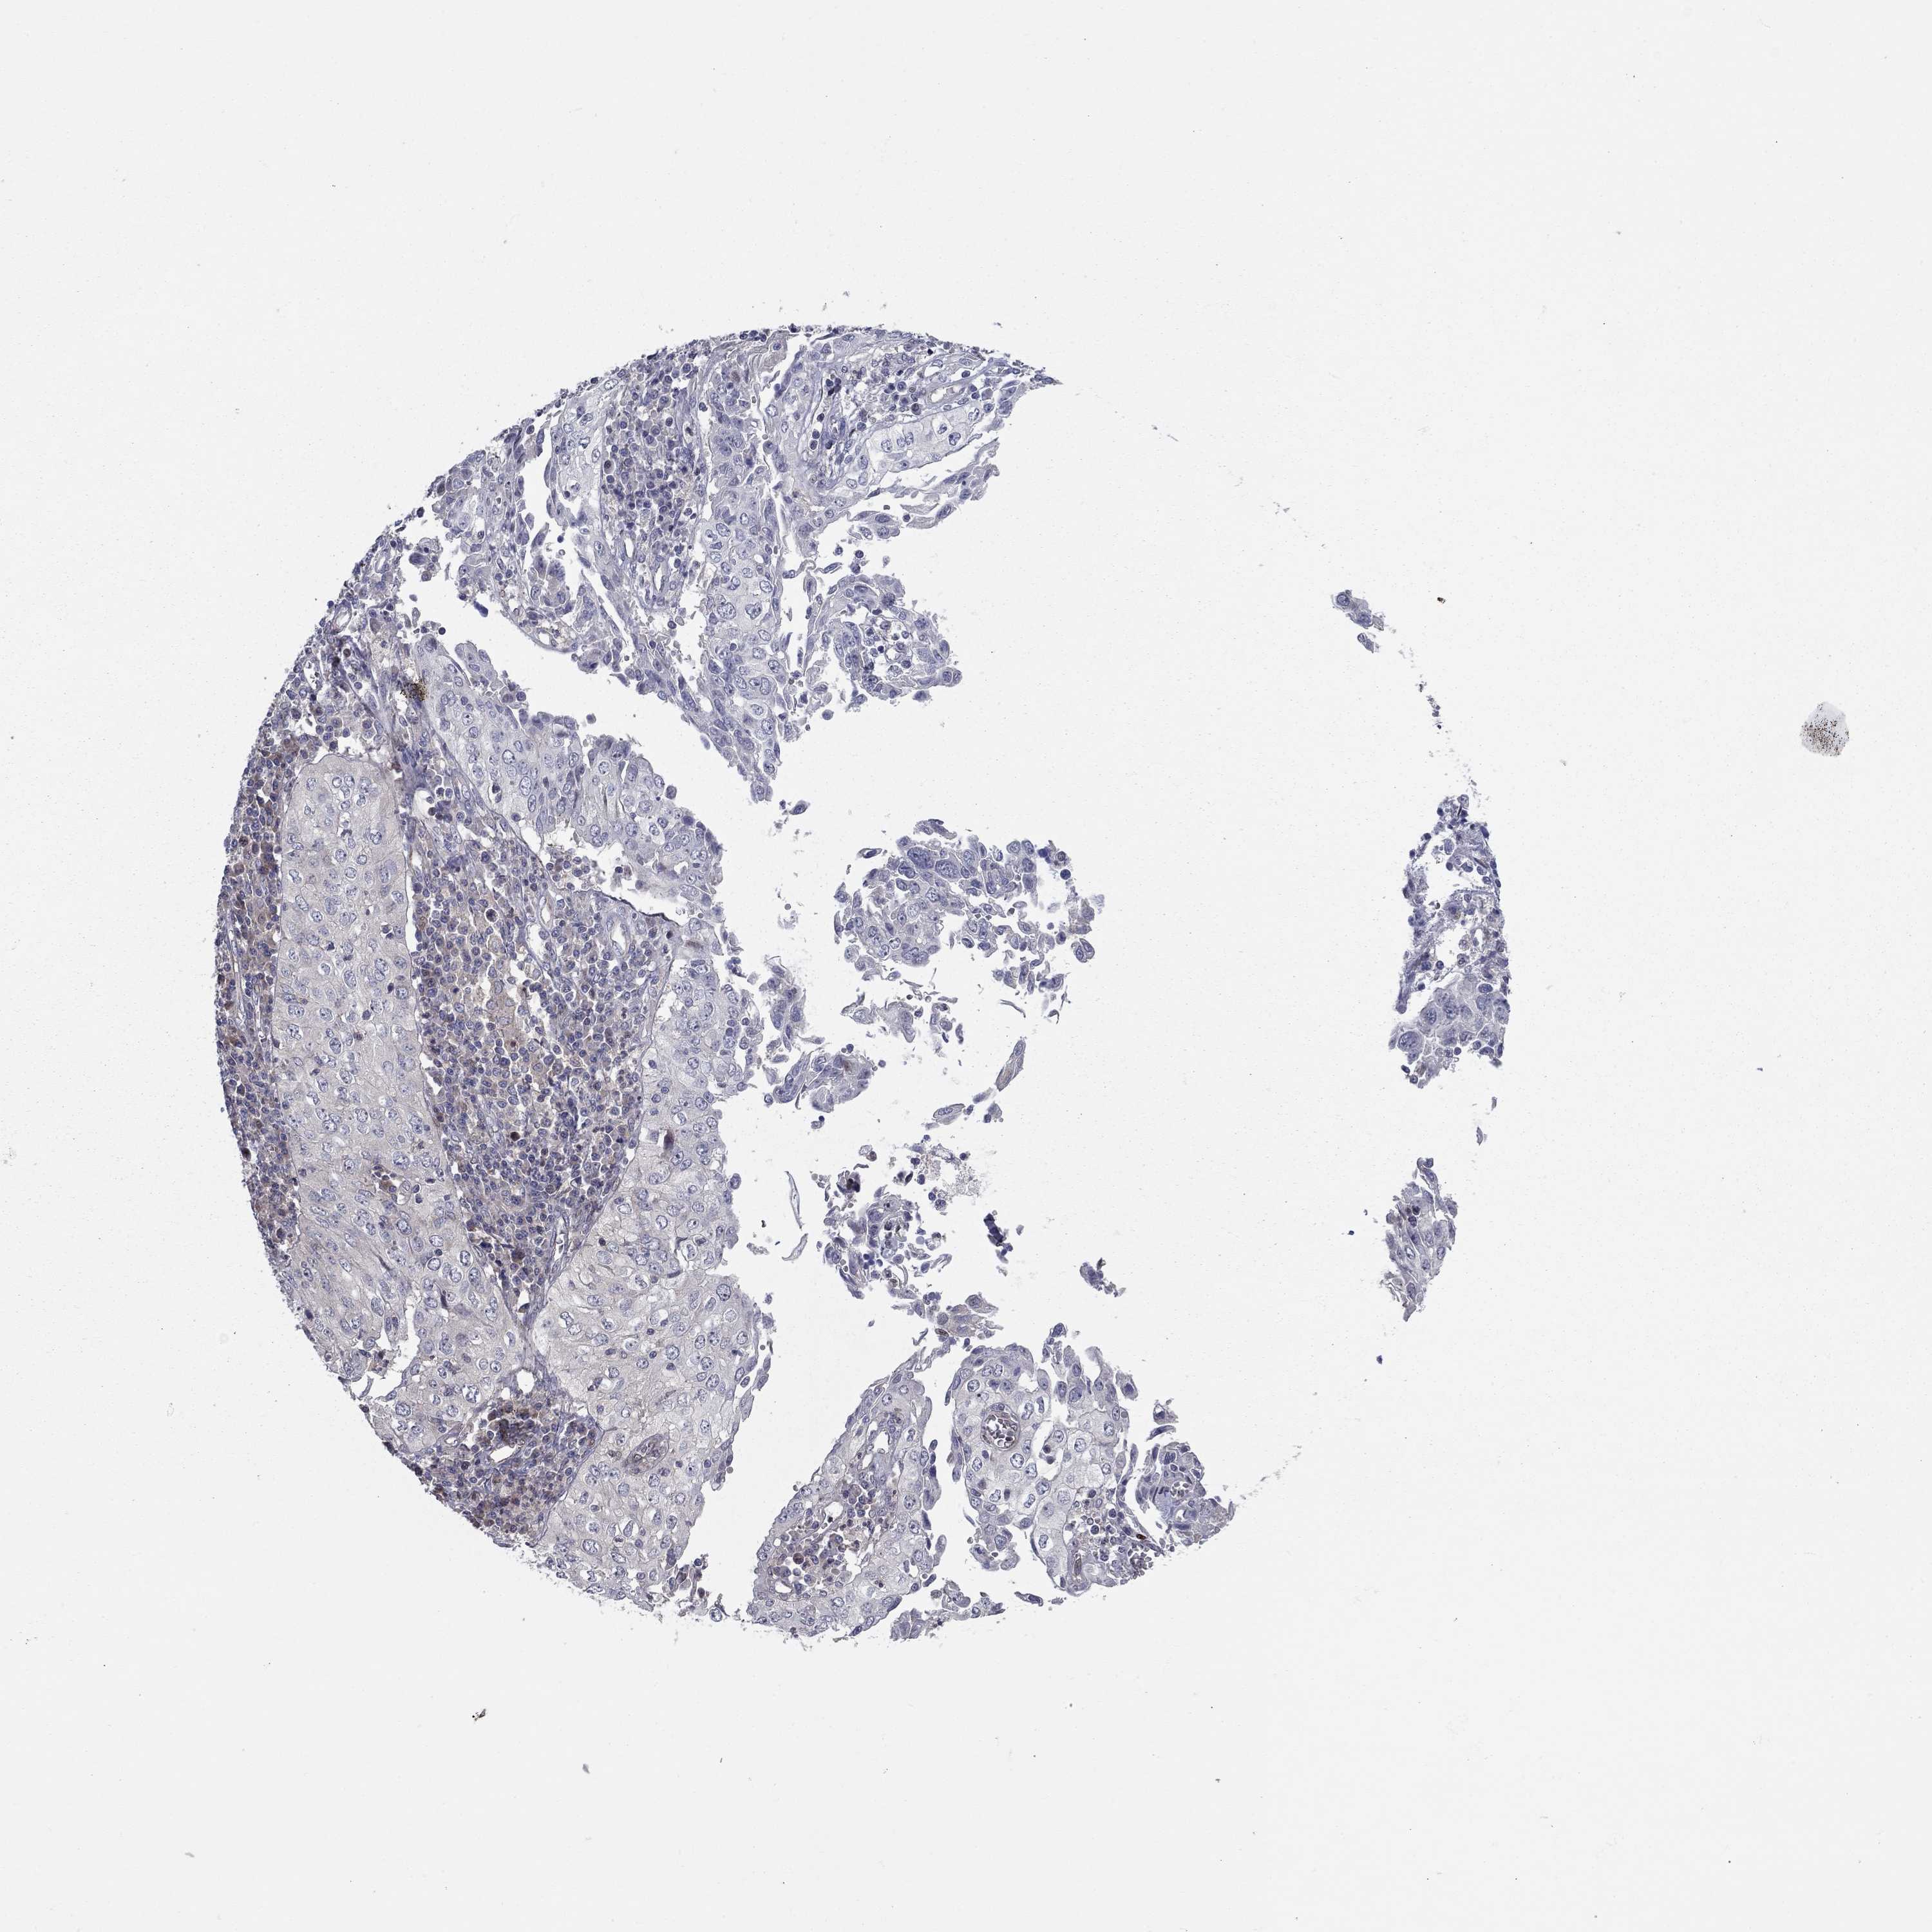

CERVICAL CANCER - Protein expressioni

A mouse-over function shows sample information and annotation data. Click on an image to view it in a full screen mode. Samples can be filtered based on level of antibody staining by selecting one or several of the following categories: high, medium, low and not detected. The assay and annotation is described here.

Note that samples used for immunohistochemistry by the Human Protein Atlas do not correspond to samples in the TCGA dataset.

Antibody stainingi

Antibody staining in the annotated cell types in the current human tissue is reported as not detected, low, medium, or high, based on conventional immunohistochemistry profiling in selected tissues. This score is based on the combination of the staining intensity and fraction of stained cells.

Each image is clickable and will lead to virtual microscopy that enables deeper exploration of all samples and also displays staining intensity scores, fraction scores and subcellular localization as well as patient and tissue information for each sample.

Antibody HPA073007

Staining

High

Medium

Low

Not detected

Intensity

Strong

Moderate

Weak

Negative

Quantity

>75%

75%-25%

<25%

None

Location

Nuclear

Cytoplasmic/membranous

Cytoplasmic/membranous,nuclear

Squamous cell carcinoma, NOS

Adenocarcinoma, NOS